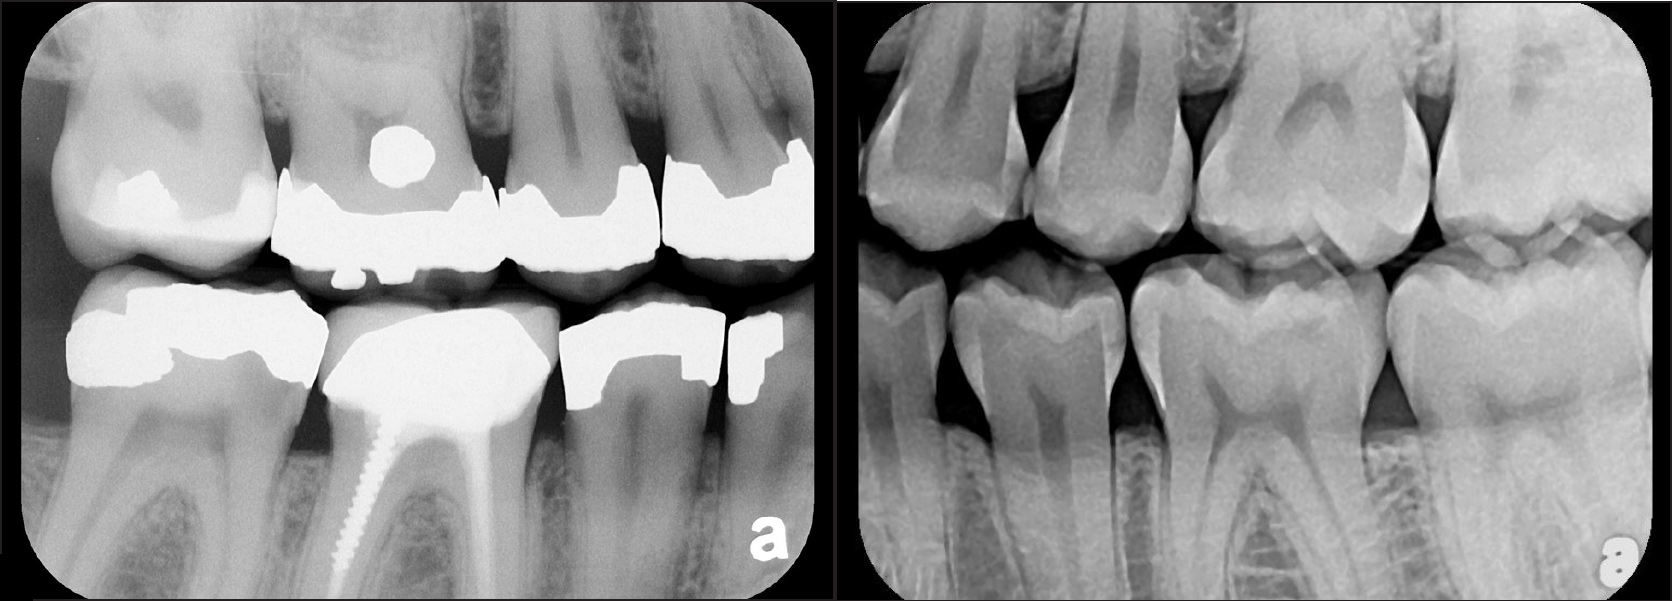

There are two specific types of DIDR sensor systems available to dentists in the marketplace: the hard-wired (HW) sensor and the photostimulable phosphor (PSP) sensor,1,2 also commonly known as phosphor "plates." A desirable feature common to both modalities is the ability to expose either bitewing (BW) or PA radiographic images. The BW radiograph (Figure 1) is usually considered more appropriate for caries detection, whereas the PA (Figure 2) is diagnostic for several different anatomic and pathologic issues.7

Fig 1. Left: Representative PSP BW radiograph with multiple restorative materials of varying radiographic densities. Tooth No. 31 demonstrates deep

caries on mesial aspect beneath the restorative. Radiolucency of carious lesion results from the low relative density of caries compared with healthy

tooth structure. Right: PSP BW radiograph optimized for view of multiple interproximal carious lesions.

Figure 1